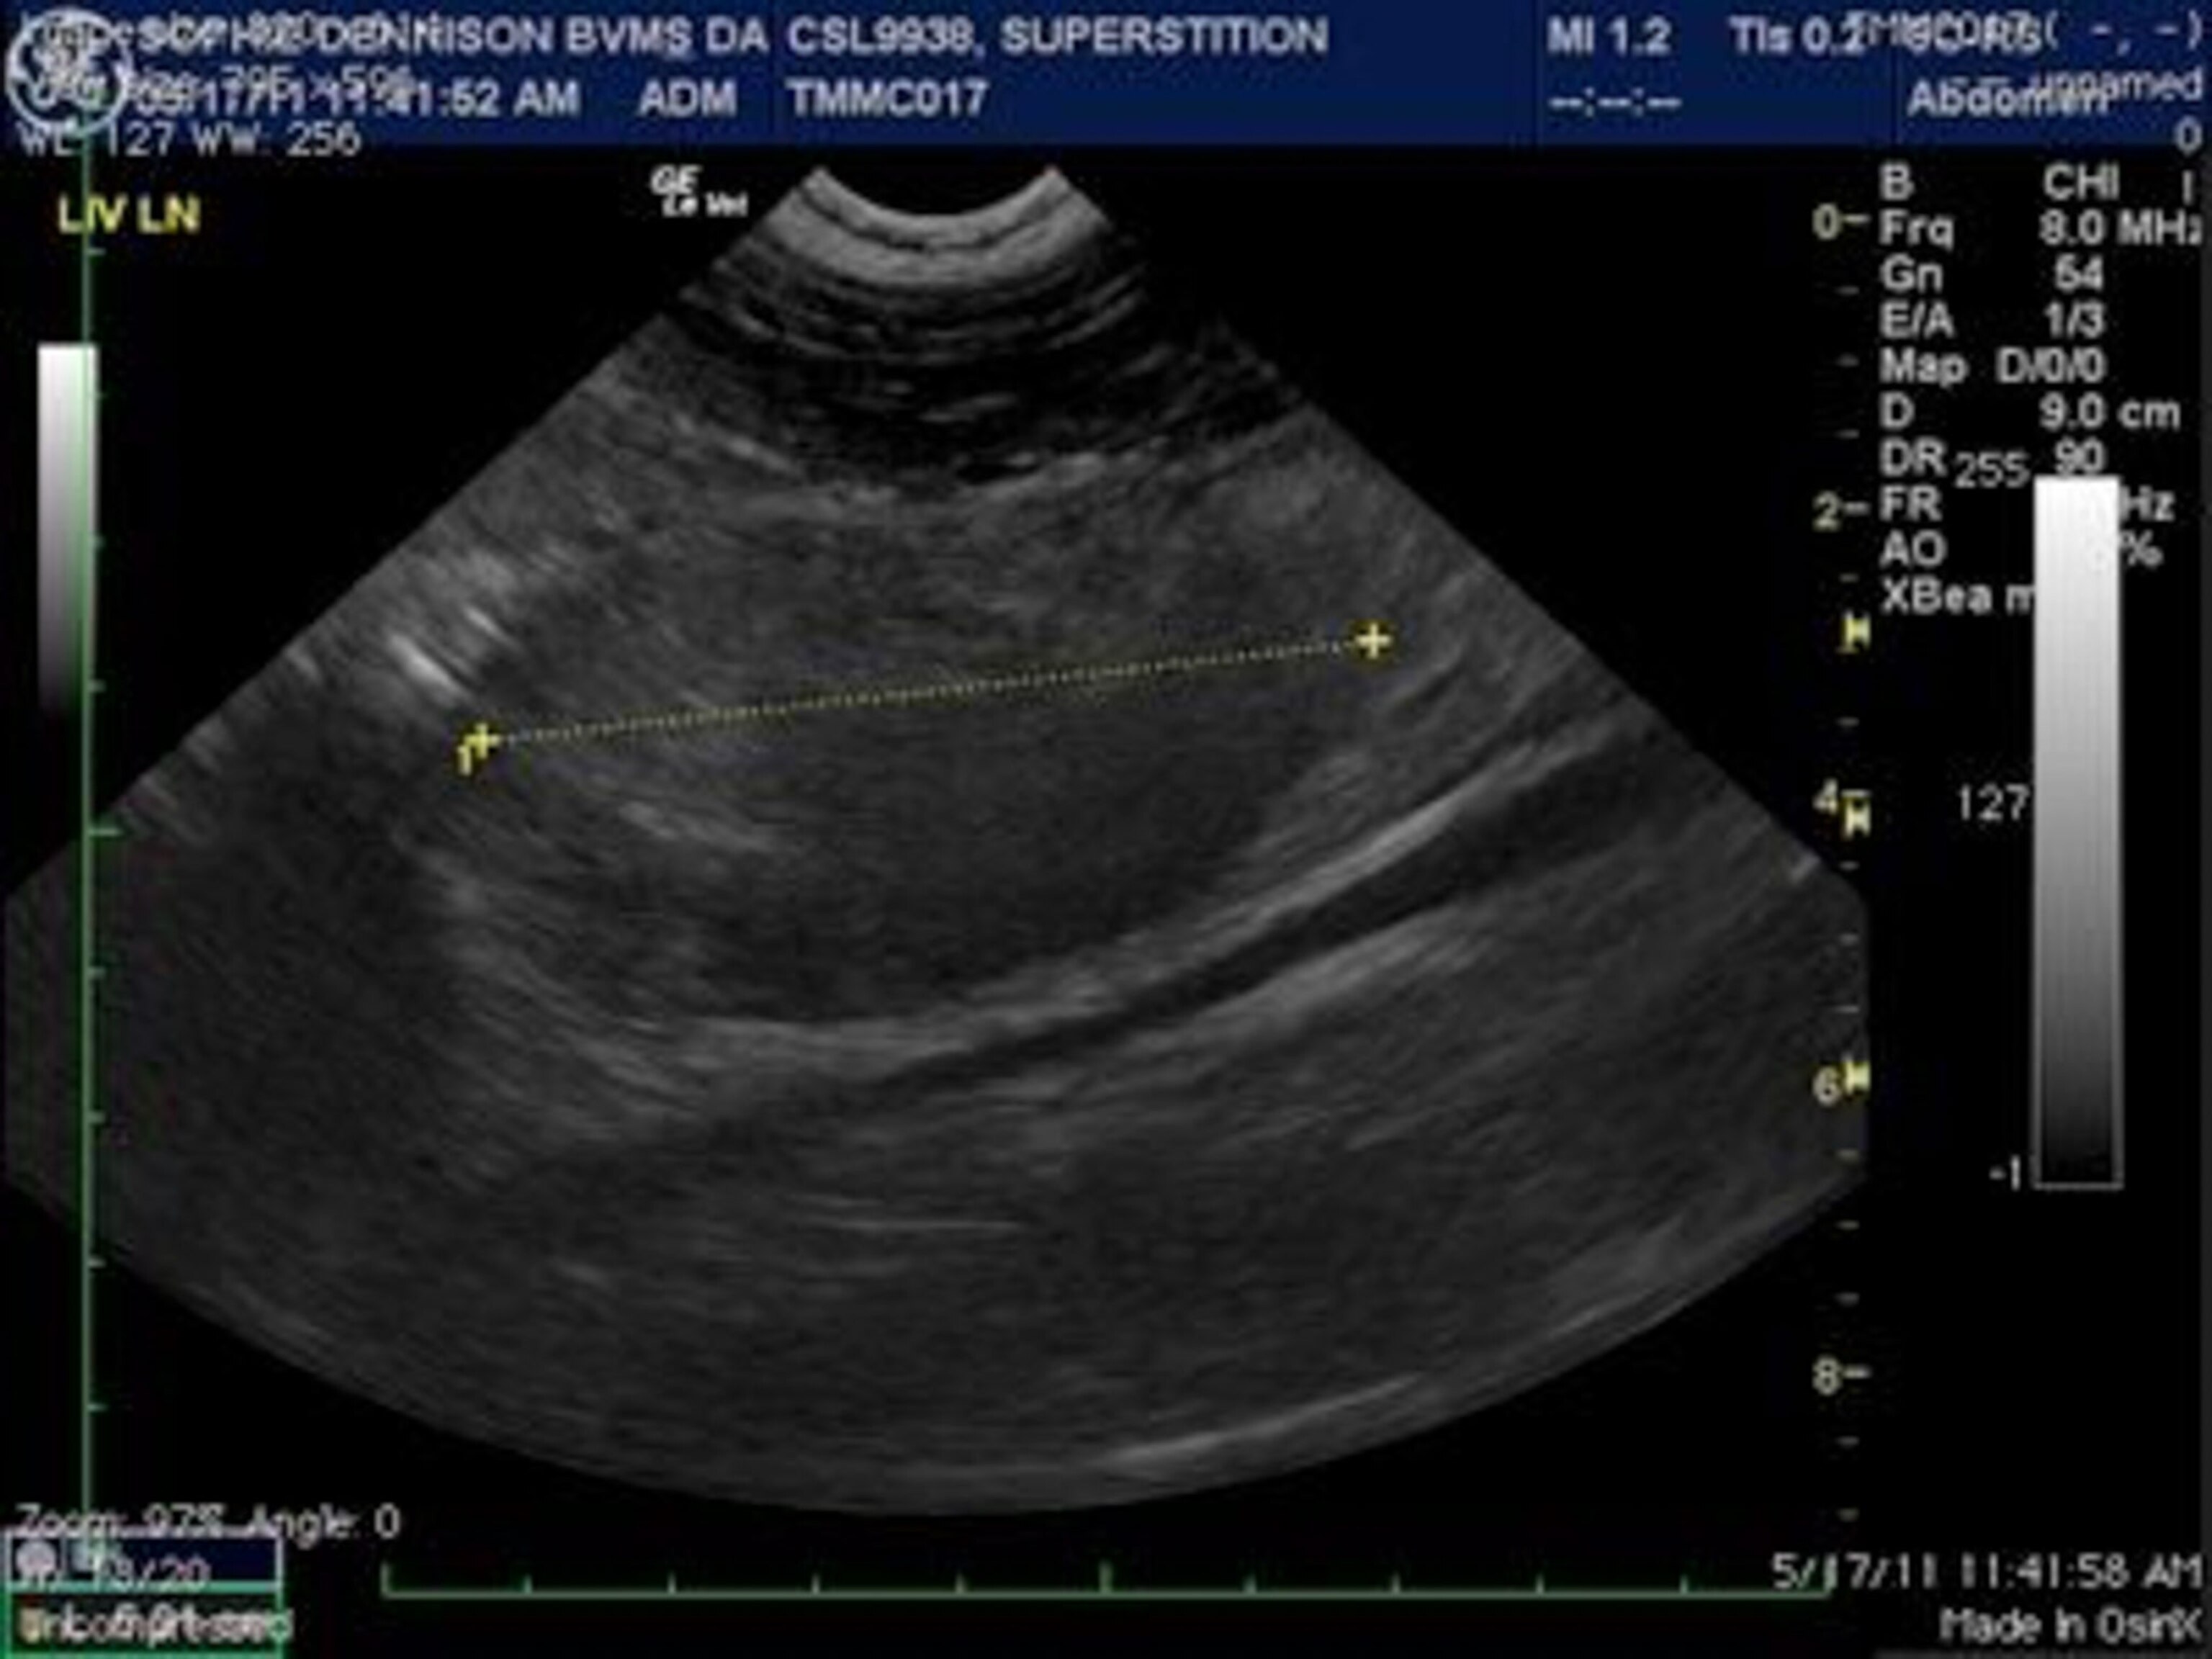

“I think we’ve got a case,” says Deming, an animal virologist and fellow at the Marine Mammal Center, a nonprofit rescue and research institution perched on the Marin Headlands across the Golden Gate Bridge from San Francisco. “The uterus is dilated and the lining is thickened like endometriosis.”

Deming thinks the animal may be the latest victim of a scourge of genital cancers afflicting California’s sea lions.

Gulland, sun-bleached and trim after years of rescuing ocean animals, is skeptical. She comes from the look-first-for-the-normal school of diagnosis for wildlife. This sea lion, she suggests, may have been pregnant, aborted, and not yet returned to a normal size uterus. She promises, though, to examine the animal before she flies to Mexico to look at the corpses of two rare vaquita porpoises that washed up in the Gulf of California. Deming is appreciative, knowing further tests will reveal whether the animal’s tissue is cancerous. “Everybody wants to work with Frances,” says Deming. “Everybody.”